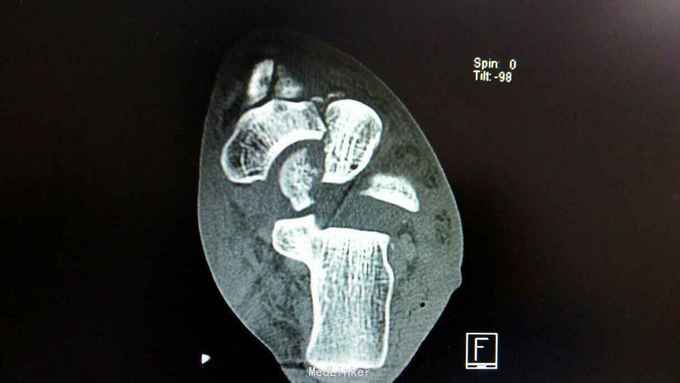

距骨骨折并脱位

骨折 距骨骨折

重物砸伤左足疼痛畸形14小时。

左踝至中足肿胀,左足内翻畸形,皮肤可见少许细小水泡,压痛,足背动脉搏动可,足趾活动可,感麻木。

距骨骨折并脱位 入院行闭合手法复位失败,予以跟骨牵引5天,石膏外固定3天,皮肤水泡、肿胀消退后行,距骨骨折脱位切开复位内固定+距舟关节融合。术后支具外固定,勿负重3个月。

延期复位对距骨血运影响?距骨后缘骨折块不处理对踝关节影响如何?